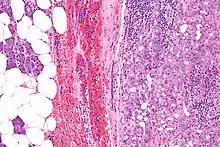

| Micrograph of an acinic cell carcinoma (right of image) and acinar glands (parotid gland - left of image). H&E stain. | |

Basophilic, bland cells similar to acinar cells. Growth pattern: solid - acinar cells, microcytic - small cystic spaces mucinous or eosinophilic, papillary-cystic - large cystic lined by epithelium, follicular - similar to thyroid tissue.

These tumors, which resemble serous acinar cells, vary in their behavior from locally aggressive to blatantly malignant.